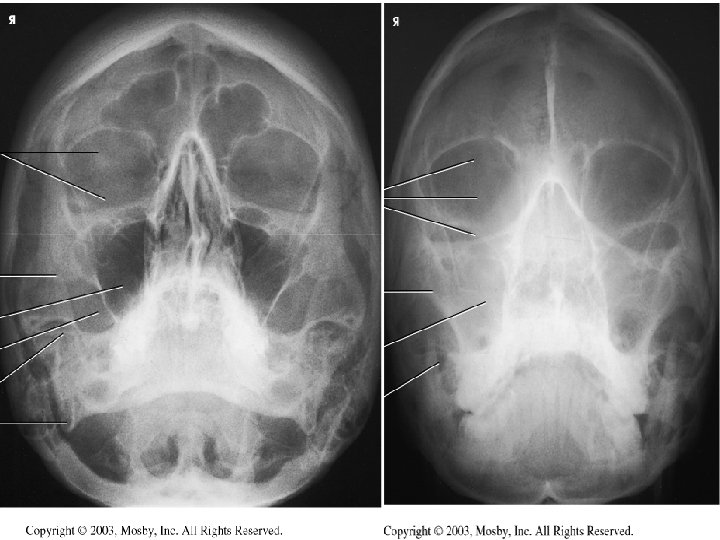

Waters Radiograph n Distance from lateral border of skull and orbit equal on each side n Petrous ridges projected immediately below maxillary sinuses

Trauma

Reverse Waters n Supine n Extend neck so OML is 37 degree with plane of IR n MML and MSP perp n Suspend respiration n CR perpendicular and enters acanthion

Reverse Waters Radiograph n Distance from lateral border of skull and orbit equal on each side n Petrous ridges projected immediately below maxillary sinuses